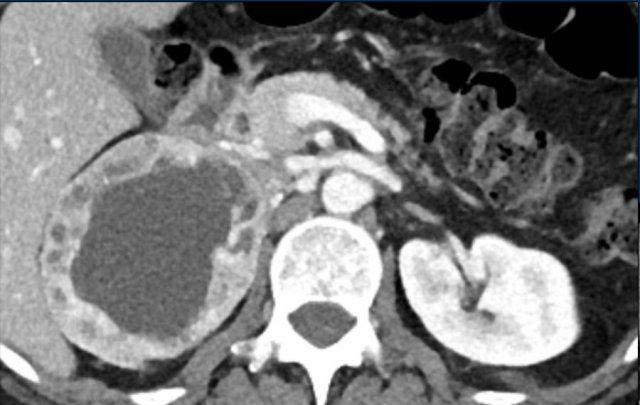

Hình ảnh cho thấy một khối không đồng nhất, bờ không rõ, kích thước lớn hơn 4 cm.

Có vùng trung tâm ngấm thuốc kém, nhiều khả năng là do hoại tử trung tâm.

Trong trường hợp cụ thể này, sinh thiết đã được thực hiện và cho thấy ung thư biểu mô tuyến, có thể xuất phát từ ung thư phổi nguyên phát.

Tuy nhiên, điều đáng ngạc nhiên là phân tích hình ảnh toàn diện, bao gồm cả FDG PET-CT, không phát hiện được khối u nguyên phát.